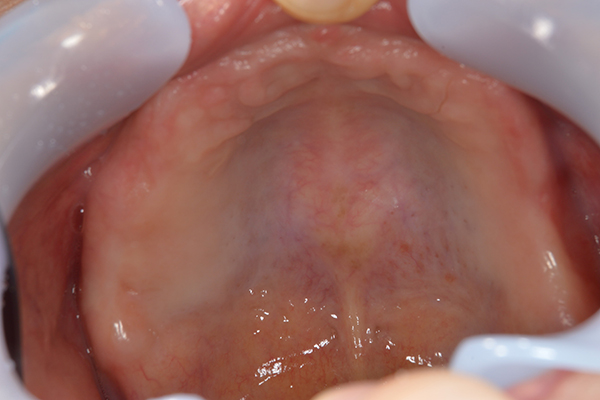

右上と左下の歯がない方です。 上の入れ歯の安定が悪く、作り直したいとのことでいらっしゃいました。 今お使いの上の入れ歯を見てみると、口蓋部分が抜けており、安定性に欠ける構造になっていました。この入れ歯はノンメタルクラスプデンチャーといって、金属のバネを使用しない 入れ歯になります。これは見た目は良いのですが、歯への負担が大きいことと、入れ歯自体がやわらかいため、噛むには不便なことがあります。

入れ歯は極力薄くするために金属を使用しました。しっかり噛める様にするため、ノンメタルクラスプデンチャーにはしませんでした。

上の入れ歯(表)

上の入れ歯(裏)

下の入れ歯

入れ歯を入れた状態のお口の中の写真です。バネも極力目立たないように作成しています。

年齢 70代・女性

主訴 上の入れ歯の安定が悪く、作り直したい

治療期間 5ヶ月

治療費 .診査診断:55,000円

.インプラント埋入:165,000円

.アバットメント:33,000円

.義歯:330,000円

治療方針 右片側のみ奥歯がない方です。

この様な場合入れ歯は反対側に維持を求めるため、大きな入れ歯になりがちです。

そのため違和感が強いことがおおいです。

また、片側だけないですので、安定もむずかしくなります。

そこで、安定をよくするために、右の奥歯の位置にインプラントをいれて、義歯が揺れない様にすることにしました。

治療内容 レントゲンをみて最低限の長さのインプラントを右上の奥歯の位置に埋入しました。インプラントと骨の結合(オッセオインテグレーション)と歯肉の治癒を待ち、アバットメントをいれて型取りをして、入れ歯を作成しました。極力薄くするために、金属をもちいた入れ歯にしました。

特記事項 インプラントは必ず成功するというものではありません。 また治癒も人それぞれで、長くかかることもあります。 入れ歯を入れ終わったあとも、アバットメントが緩んできたり、入れ歯が歯ぐきにあたって痛いところもでてきますので、調整は必要になります。